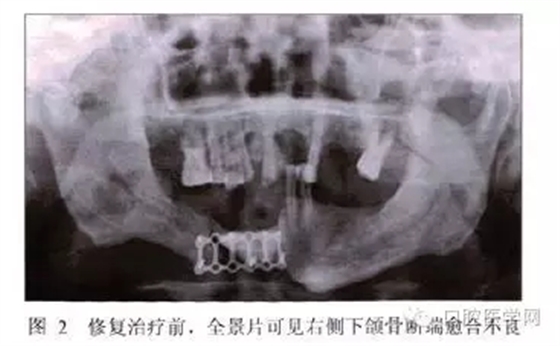

全景片示:下頜骨右側(cè)有不透光骨固定物,斷端結(jié)合處有透光影,余留牙處略有骨吸收,根尖周未見明顯異常(圖2)。